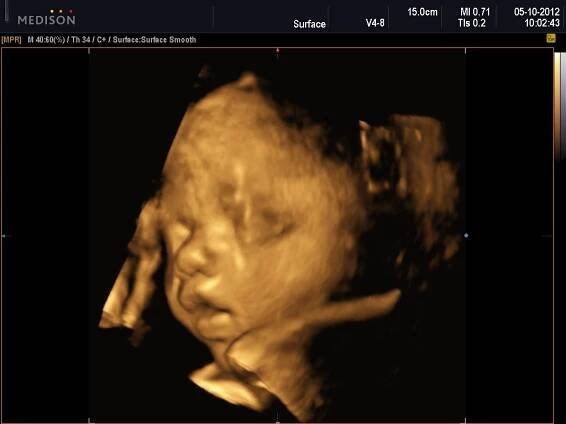

3D ultrazvuk 23.týden

Jaký je rozdíl mezi 3D a 4D ultrazvukem?Snímek 3D je dokonale plastická fotografie vašeho miminka, zcela reálná v daném čase a prostoru. V případě 4D zobrazení jde technický pokrok ještě dále a vy máte díky této technologii možnost vidět i reálný pohyb miminka natočený na videozáznam.

Kdy se tento ultrazvuk provádí?Za ideální čas pro 3D a 4D snímek je považované období od 24. do 28. týdne těhotenství. Každé středisko ale uvádí jiné týdny, obvykle však v rozptylu od 20. do 31. týdne.

Již během těhotenství máme možnost zachytit tvář plodu pomocí 3D/4D zobrazení na přístroji GE Voluson E10. Z kliniky Gennet si tak můžete odnést vůbec první opravdovou fotografii svého dítěte!